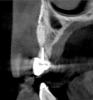

Tomographic images revealed a large tridimensional defect, with vertical and horizontal loss of bone extending to the apical third of teeth Nos. 6 and 8. Additionally, a buccal bone dehiscence was evident on tooth No. 5, and thin labial plates secondary to the orthodontic movement were present in several areas (Figure 3 and Figure 4).

Fig 4. Tomographic images revealed a tridimensional defect extending to the apical third of teeth Nos. 6 and 8, a buccal bone dehiscence on tooth No. 5, and associated thin labial plates.

Figure 4